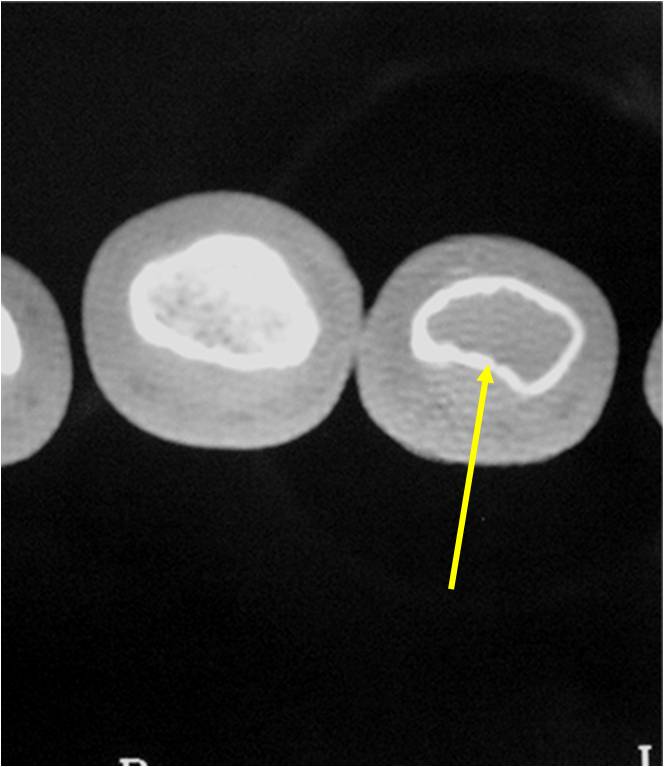

- There should never be any cortical destruction nor a soft tissue component. If this exists then the tumor must be a chondrosarcoma.

- Endosteal scalloping and cortical expansion is acceptable for phalangeal tumors. In most benign long bone cartilage tumors there is minimal endosteal scalloping but there should be no cortical expansion nor thickening. There should be no cortical destruction and no soft tissue component associated with an enchondroma. Cortical destruction, periosteal thickening, cortical expansion and a soft tissue component indicates a chondrosarcoma of the long bone.

- Endosteal erosion>2/3 cortical thickness on a CT scan